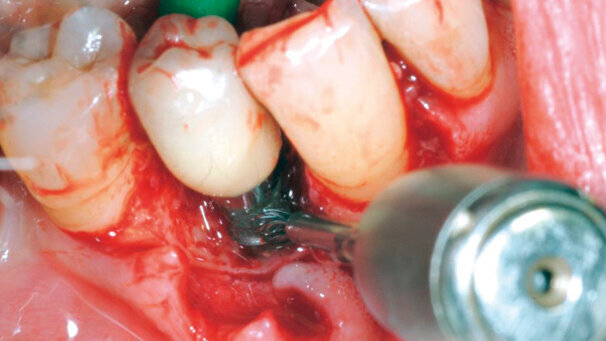

Il mio contributo sul Journal of Clinical Peirodontology, nostra rivista di riferimento, prende in esame due passaggi fondamentali: la decontaminazione delle superfici implantari, effettuabile con tecniche varie e più o meno sofisticate e l’approccio rigenerativo/ricostruttivo mediante osso deproteinizzato bovino, fonte di risultati eccellenti e stabili nel tempo.

È indicata quando la perimplantite ha compromesso l’osso di supporto, creando un difetto intraosseo verticale, cercando quindi di ridurre il riassorbimento osseo. Non lo è invece quando abbiamo un riassorbimento orizzontale, quando, insomma non ci sono crateri da colmare.